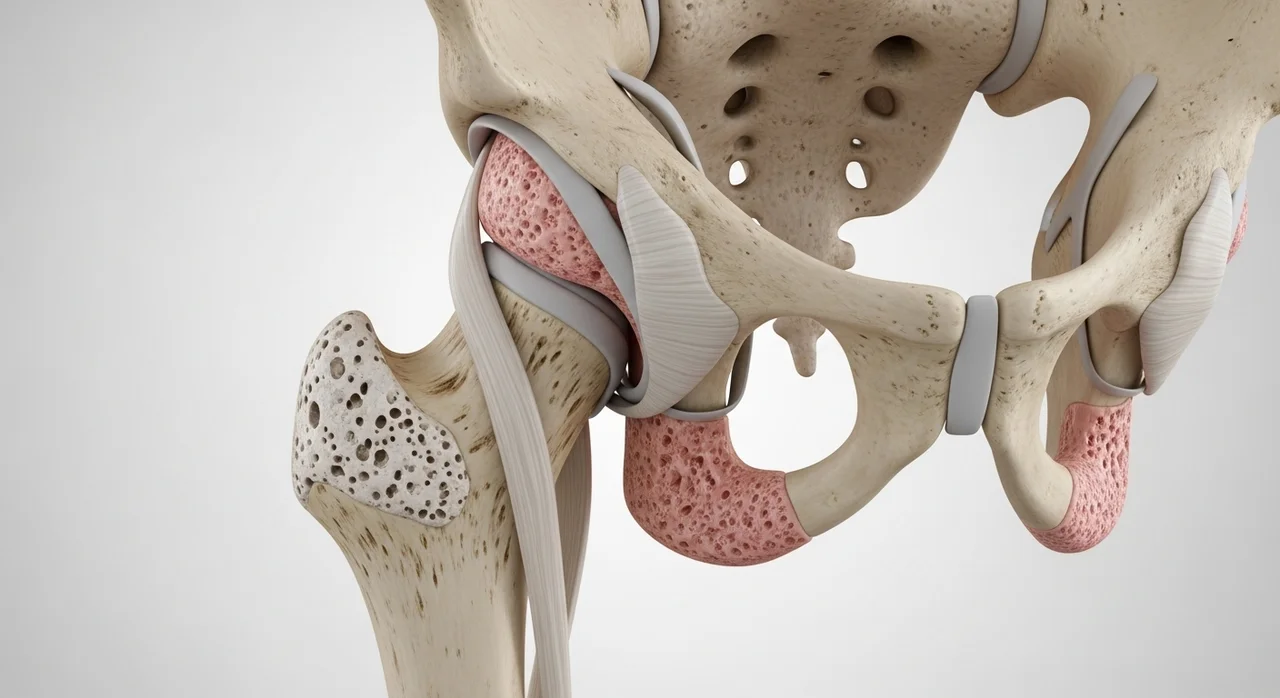

가장 위험한 고관절 골절, 왜 '사망'까지 언급될까요?

고관절 골절은 대퇴골(허벅지 뼈)의 윗부분이 부러지는 것을 말합니다. 주로 빙판길에서 넘어지거나 욕실에서 미끄러질 때 발생하는데요, 문제는 골절 자체보다 그 이후의 상황입니다.

⚠️ 주의사항: 고관절 골절의 연쇄 반응

고관절이 부러지면 스스로 일어날 수 없습니다. 장기간 누워 지내게 되면 폐렴, 욕창, 심혈관 질환 등 2차 합병증이 급격히 진행되어 고령자의 경우 생명이 위험해질 수 있습니다.

실제로 통계에 따르면 고관절 골절을 겪은 노인 5명 중 1명은 1년 이내에 사망한다는 보고가 있을 정도예요. 따라서 고관절 부위는 평소 근력 운동을 통해 주변 근육을 강화하고, 집안의 문턱을 없애는 등 낙상 예방에 최선을 다해야 합니다.